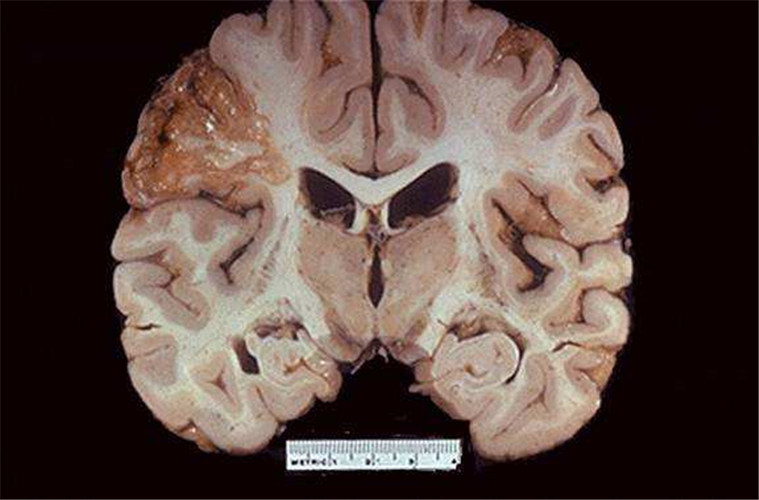

血栓性腦梗塞

液化性腦梗塞